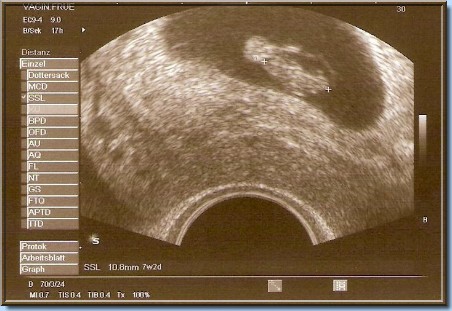

Unser kleiner Zwerg

in der 7.SSW